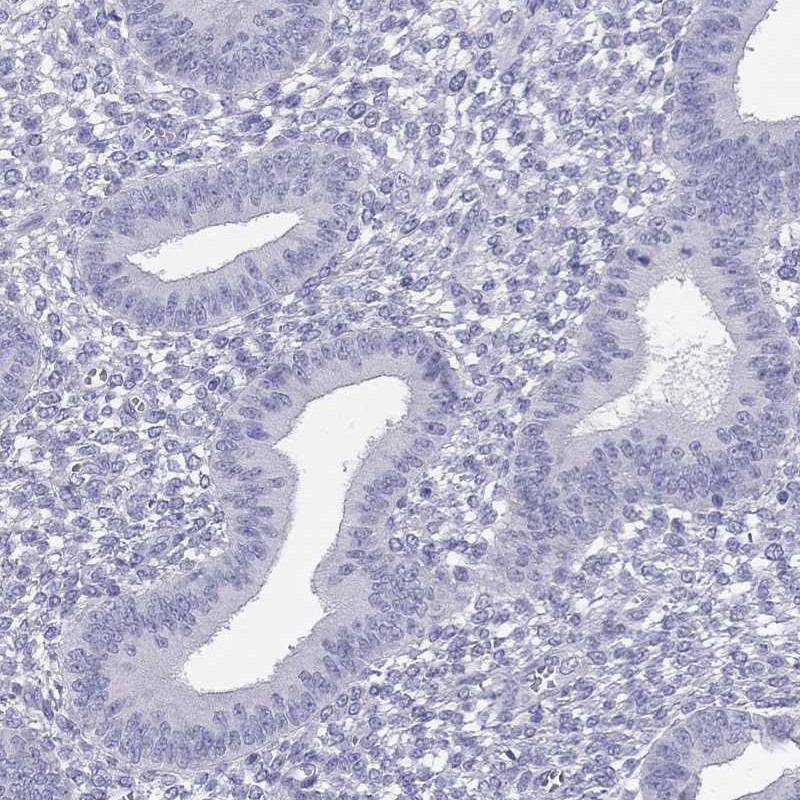

Learn how we validate our antibodies, how we secure their reproducibility, and why we apply enhanced validation. Our antibodies are validated in IHC, ICC-IF, and WB.